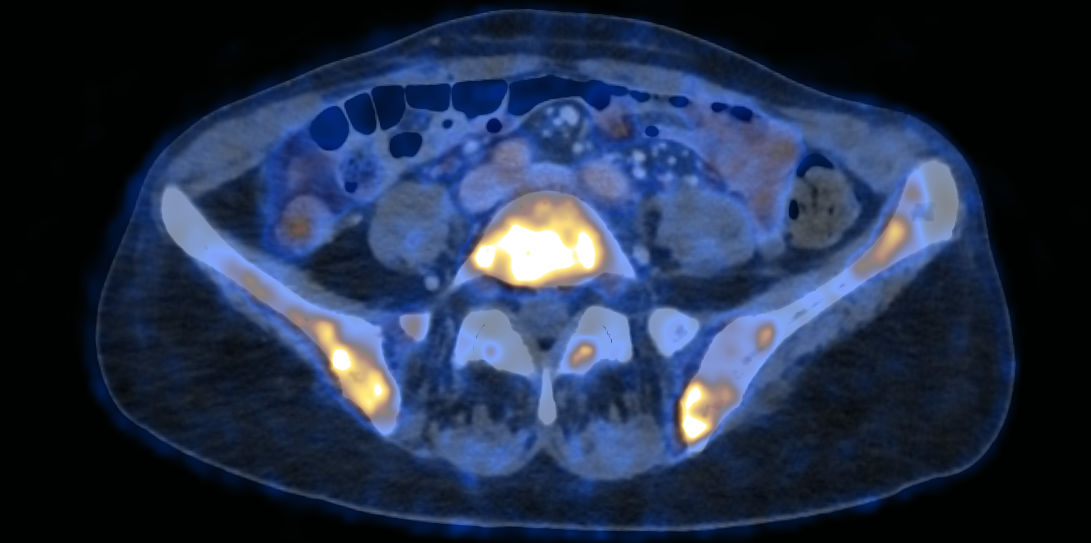

Um das Fortschreiten von Knochenmetastasen sowie einhergehende Folgen wie Schmerzen und Brüche zu verhindern, erhalten Brustkrebspatientinnen mit Knochenmetastasen Medikamente wie Bisphosphonat oder Denosumab. Diese Substanzen beeinflussen den Knochenstoffwechsel, können aber eine sogenannte Medikamenten-assoziierte Kiefernekrose auslösen. Bei derartigen Kiefernekrosen kommt es zum Absterben des Kieferknochens. Aber wie häufig tritt diese gefürchtete Nebenwirkung auf? Antworten auf diese Frage liefert eine Studie der Medizinischen Universität Innsbruck, die im renommierten Journal of Clinical Oncology (Impact Faktor 42,1) veröffentlicht worden ist.

Ein interdisziplinäres Forschungsteam unter der Leitung von Oberärztin Christine Brunner von der Univ.-Klinik für Gynäkologie und Geburtshilfe (Direktor: Christian Marth) und dem Facharzt für Mund-, Kiefer- und Gesichtschirurgie Johannes Laimer hat nun wichtige Erkenntnisse zu dieser bisher als sehr seltene Nebenwirkung eingestuften Erkrankung gewonnen. Dafür wurden Daten von Tiroler Brustkrebspatientinnen mit Knochenmetastasen aus den Jahren 2000 bis 2020 analysiert. Es konnten die Patientinnen aller neun Tiroler Krankenanstalten erfasst werden. Die Ergebnisse der statistischen Auswertung lieferten wichtige Erkenntnisse hinsichtlich der Häufigkeit des Auftretens dieser Nebenwirkung, sodass in der Folge neue Standards zur Prävention und Früherkennung definiert werden konnten. „Wir haben hier interdisziplinär gearbeitet und konnten so zeigen, dass es durchschnittlich bei 8,8 Prozent der Brustkrebspatientinnen zur Entwicklung einer Kiefernekrose kam. Dieser Prozentsatz ist deutlich höher als die bisher in der internationalen Literatur angegebenen Werte. Durchschnittlich dauerte es 4,6 Jahre bis Patientinnen mit Denosumab eine Kiefernekrose entwickelten, im Gegensatz zu 5,1 Jahren bei der Einnahme nach Bisphosphonaten,“ erklärt Erstautorin Christine Brunner.

Die spezielle Behandlung mit Bisphosphonat oder Denosumab, die eine Ausbreitung der Knochenmetastasen verlangsamen und über Jahre stabil erhalten sollen, erfolgt zielgerichtet. „Das ist eine sehr effektive Therapie und erhöht die Lebensqualität der betroffenen Patientinnen“, erklärt Christine Brunner. Dass es nach Einnahme solcher Medikamente zu Infektionen des Kieferknochens bis hin zum Zahn- und Knochenverlust im Kieferbereich mit potentiell schwerwiegender Beeinträchtigung der Lebensqualität kommen kann, ist schon seit vielen Jahren bekannt. Vor diesem Hintergrund wurde an der Innsbrucker Univ.-Klinik für Mund-, Kiefer- und Gesichtschirurgie bereits 2016 eine Spezialambulanz für diese Medikamenten-assoziierte Kiefernekrosen eingerichtet.